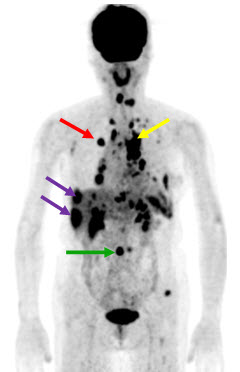

Hình 4 (a, b) cho thấy giá trị của PET/CT trong đánh giá giai đoạn của ung thư vú. Bệnh nhân Nguyễn Th. T. Tr., nữ, 63 tuổi, chẩn đoán là ung thư vú. Kết quả PET/CT toàn thân cho thấy nhiều tổn thương di căn hạch cổ, hạch trung thất, di căn 2 phổi, gan, xương tăng hấp thu FDG.

Hình 4a. Hình PET toàn thân thấy nhiều tổn thương hạch cổ, hạch trung thất (mũi tên vàng), phổi (mũi tên đỏ), gan (mũi tên tím) và xương (mũi tên xanh) tăng hấp thu FDG.

Hình 4b. Hình PET/CT ở mặt phẳng cắt ngang thấy tổn thương di căn phổi (mũi tên đỏ) và di căn gan (mũi tên da cam).

(Nguồn: Mai Trọng Khoa – Trung tâm Y học hạt nhân và ung bướu – BV Bạch Mai)